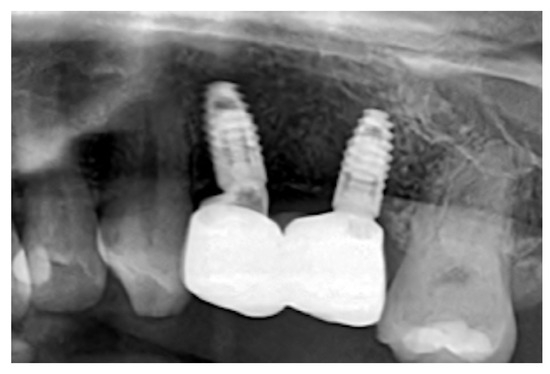

Long-Term Clinical Outcome of a Surgically Treated Ameloblastoma: Over a Decade of Follow-Up and Oral Rehabilitation

Background: Ameloblastomas account for roughly 1% of all jaw tumours and cysts, typically manifesting as slow-growing, painless swellings that expand both buccal and lingual cortical plates and may infiltrate adjacent soft tissue, often leading to a delayed diagnosis. These benign tumours, characterized [...] Read more.

Background: Ameloblastomas account for roughly 1% of all jaw tumours and cysts, typically manifesting as slow-growing, painless swellings that expand both buccal and lingual cortical plates and may infiltrate adjacent soft tissue, often leading to a delayed diagnosis. These benign tumours, characterized by local invasiveness, originate from epithelial tissues and may develop from dental lamina cell rests, the enamel apparatus, the epithelial lining of odontogenic cysts, or basal epithelial cells of the oral mucosa. Methods: This paper aims to describe the comprehensive and interdisciplinary management of an extensive ameloblastoma in a 16-year-old patient, emphasizing the diagnostic challenges, surgical resection, reconstructive procedures, and subsequent oral rehabilitation. Results: At the eleven-year follow-up, clinical and radiographic examinations showed no signs of tumour recurrence. The patient presented no symptoms, indicating neither pain nor functional impairment. The prosthetic rehabilitation utilizing implant-supported fixed restorations was successfully completed, resulting in satisfactory masticatory function and aesthetics. This case adds to the existing evidence on the management of extensive ameloblastomas by demonstrating successful long-term outcomes following interdisciplinary surgical reconstruction and rehabilitation. Conclusions: The presented case highlights the complexity of restoring the lost tissues and functions, as well as the long-term clinical, functional, and aesthetic outcomes over an eleven-years follow-up period. Full article

(This article belongs to the Special Issue Bone Regeneration and Tissue Reconstruction in Dentistry)